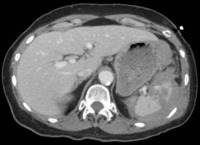

Exploración por TC que muestra laceración hepática

Colección del MetroHealth Medical Center